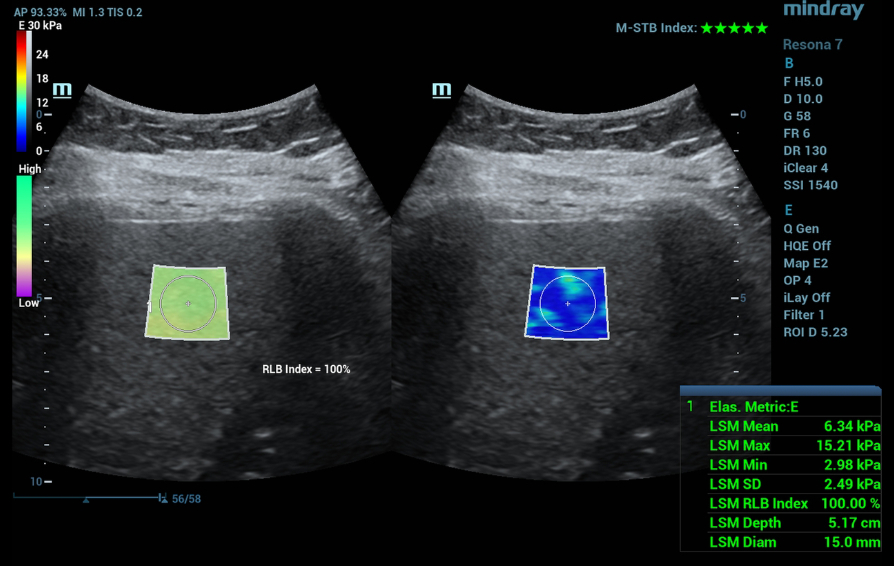

Two-dimensional shear wave elastography (2D-SWE, STE)

Two-dimensional shear wave elastography values correspond to F0-F1 stage of the fibrotic process - stiffness 6.34 kPa - clinically insignificant liver fibrosis (Figure 1).